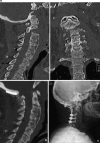

Introduction: Surgical management of upper cervical spine (UCS) unstable injuries may be challenging as the number of cases requiring this surgery collected in every single center is small. This retrospective study was conducted to analyze the radiographic and clinical results in 12 patients undergoing a posterior occipito-cervical fusion by a polyaxial screws-rod-plate system.

Results: Two patients died postoperatively in Intensive Care Unit. All surviving patients achieved solid fusion at 6 months. No surviving patient had neurological deterioration postoperatively. There were no instrumentation failures or revision required. Two patients suffered from superficial occipital wound infection.

Conclusions: Although the indication to occipito-cervical fusion decreased since the new C1-C2 posterior fixation techniques were described, it remains a valid and reliable option in UCS post-traumatic instability to be applied even in emergency especially in the elderly.